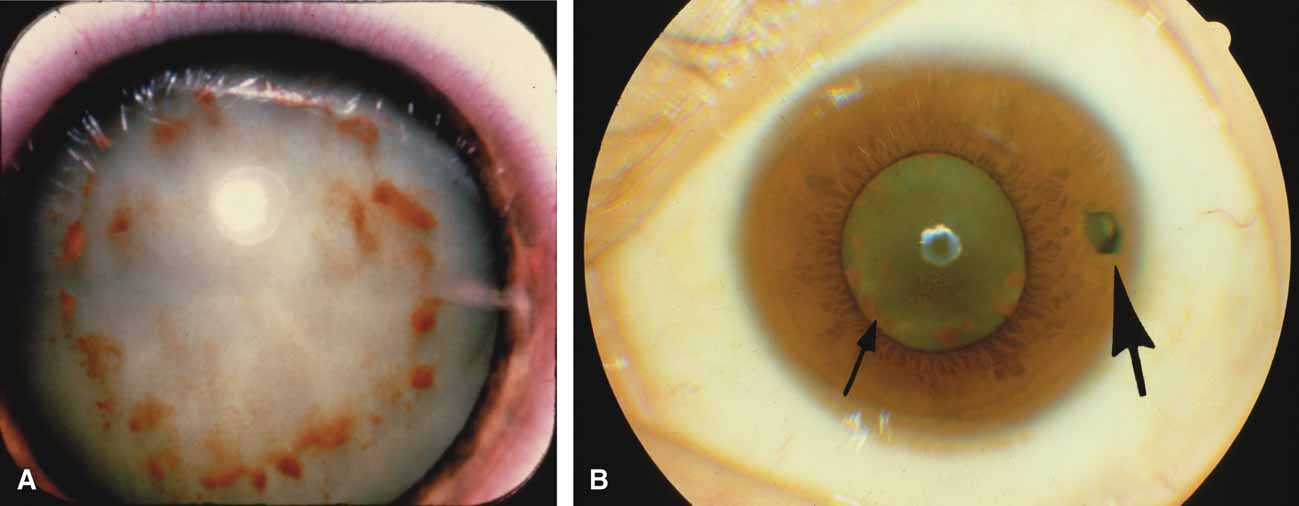

The majority of cases of ghost cell glaucoma occur following vitrectomy for diabetic retinopathy, vitreous hemorrhage due to trauma, or vitreous hemorrhage following anterior segment surgery (i.e., cataract extraction or corneal transplant). Although studies suggest that a disruption of the anterior hyaloid face may be a necessary precedent, ghost cell glaucoma probably can occur with an intact hyaloid if a sufficient quantity of vitreous blood is present.27 The clinical presentation includes acute pressure elevation, corneal edema, and lack of keratic precipitates. Minute tan cells (ghost cells) may layer out, producing a pseudohypopyon or, if admixed with blood, a “candy-striped” hypopyon. (Fig. 3) Intraocular pressure elevations after diabetic vitrectomy raise concerns regarding concomitant neovascular glaucoma. However, neovascular glaucoma rarely develops in the immediate postvitrectomy period, unless some anterior segment neovascularization was present preoperatively. Late-onset pressure elevations (> 6 to 8 weeks out) in a postvitrectomized diabetic eye usually signal neovascular glaucoma.

Over the past two decades silicone oil (dimethylpolysiloxane) has enjoyed a resurgence in the repair of complicated retinal detachments. In 1967, Watzke36 found no pressure elevation attributable to silicone but described droplets in the superior angle that result from silicone's lower specific gravity (buoyancy) compared with water. Silicone-induced glaucoma does occur, however, and one possible mechanism is an acute pupillary block due to the buoyancy of the silicone sometimes combined with overfilling the aphakic eye (Fig. 5). This can be averted by performing an inferior iridectomy and by paying careful attention to the silicone volume injected. A second mechanism involves chronic obstruction of an open angle by emulsified silicone microbubbles (more likely with low viscosity silicone, 1,000 centistokes, than high viscosity silicone, 12,500 centistokes) (Fig. 6), pigmented cells, and silicone-laden macrophages or silicone-induced fibrosis of the trabecular meshwork due to possible inherent fibrogenicity of this compound.37,38 Treatment of this open-angle glaucoma is generally medical, although silicone removal may be required. Although some studies have confirmed the presence of emulsified oil in the anterior chamber as a strong predictor of pressure elevation, others do not, suggesting that multiple factors are at play.39,40,41,42 Often this can only be seen on gonioscopy, and removal of the oil, if possible, is beneficial in some cases. Sometimes an expected pressure elevation that would otherwise occur may be muted by concomitant cyclitic membrane formation or hypotony associated with recurrent retinal detachment. The use of shunt procedures in this difficult glaucoma has led to the unusual complication of silicone oil escape into the subconjunctival space43,44 (Fig. 7). Whether placed superiorly or inferiorly, shunts should probably be avoided in these eyes unless the silicone oil can first be safely removed. Transscleral diode laser cyclophotocoagulation has been proven to be an excellent noninvasive option in treating these eyes for recalcitrant pressure elevation.45,46